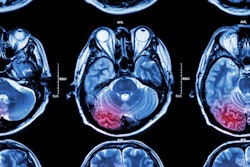

Making use of imaging features and demographic information, machine-learning algorithms predicted 90-day outcomes in patients with acute ischemic stroke, offering potential as an aid for treatment decisions, according to research published online October 24 in the American Journal of Roentgenology.

Timely and accurate outcome prediction plays an important role in making decisions on treatment and rehabilitation strategy for patients with acute ischemic stroke. Currently, this decision-making process involves assessment of biomarkers, including imaging features and demographic information, according to the researchers. They sought to use machine-learning methods to integrate these clinical and imaging variables in the acute setting to predict three-month modified Rankin scale (mRS) scores, a measure of disability, in these patients.